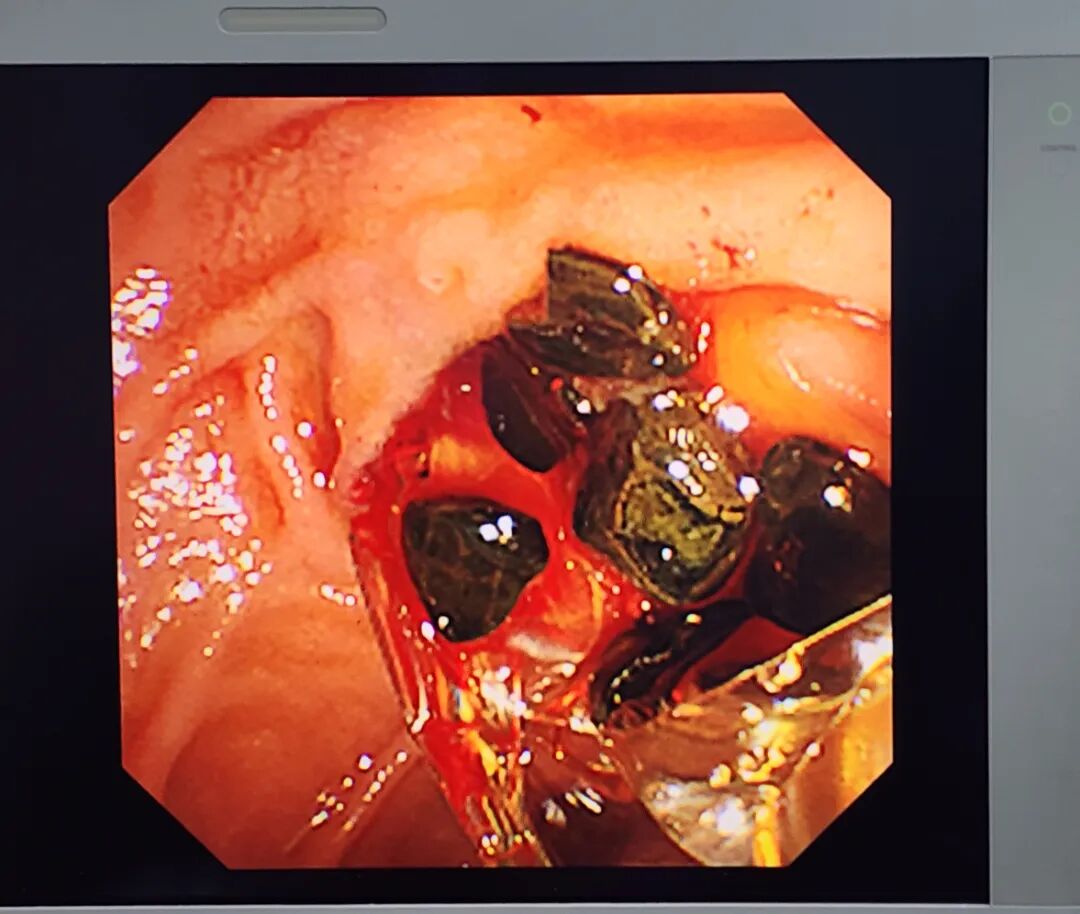

(胆总管“现场直击”,图为镜下部分结石)

MRI显示朱大叔胆总管有数十枚结石,最大直径165mm胆囊都切了很多年了,朱大叔为什么还会长结石呢?